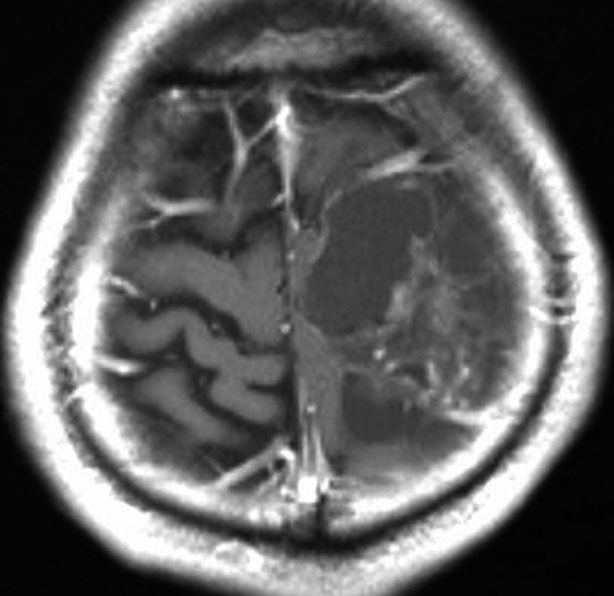

手術後に再発してもほっておく

手術で全摘出したとしても再発することがあります。左側のMRI画像は,手術後2年目に生じた再発です。8mmくらいの結節性再発がありました。15歳でしたから経過観察をしました。右の画像はその2年後です。再発腫瘍は自然に縮小していました。毛様細胞性星細胞腫は再発して増大しても,何もしないでほっておいても,自然に縮小することがあります。思春期に近い年齢層にはこの現象が期待できます。